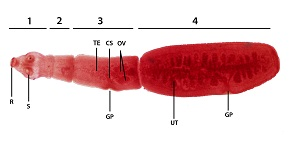

Taenia saginata

four large suckers, adult worms are flat and long

Taenia solium

four large suckers with two rows of hooks

Hymenolepis nana

two suckers with hooks

Diphyllobothrium latum

Echinococcus granulosus